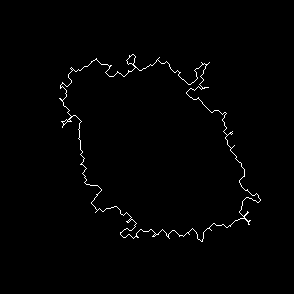

Original frames was obtained from U-118 cell line sample set. U-118 is human glyoblastoma cells widely used as model for drug testing. Also it has fibroblast like morphology and highly dynamic shape change pattern. From original microscopic images we created sets of frames containing single cell with manually outlined borders as ground truth dataset. This sets were used to have primary evaluation of segmentation successiveness. In result of described batch segmentation we obtained outline masks for each image in sequence with different accuracy of segmentation. Frames 1, 2, 9, 15, 20, 25, 40 of U-118 cell line sequence at Fig.2 an example of drastic changes of segmentation accuracy compared to manual perimeter detection.

(g) Frame 1, algorithm segmentation

Refer to caption

(h) Frame 2, algorithm segmentation

(i) Frame 9, algorithm segmentation

(j) Frame 15, algorithm segmentation

(k) Frame 25, algorithm segmentation

(l) Frame 40, algorithm segmentation

(m) Frame 1, manual segmentation

(n) Frame 2, manual segmentation

(o) Frame 9, manual segmentation

(p) Frame 15, manual segmentation

(q) Frame 25, manual segmentation

(r) Frame 40, manual segmentation

Figure 2: Original images sample sequence, results of algorithm processed and manually outlined cell contour. The image i and j of sequence show bad segmentation accuracy compared to manually outlined images, while rest of sequence has acceptable level.